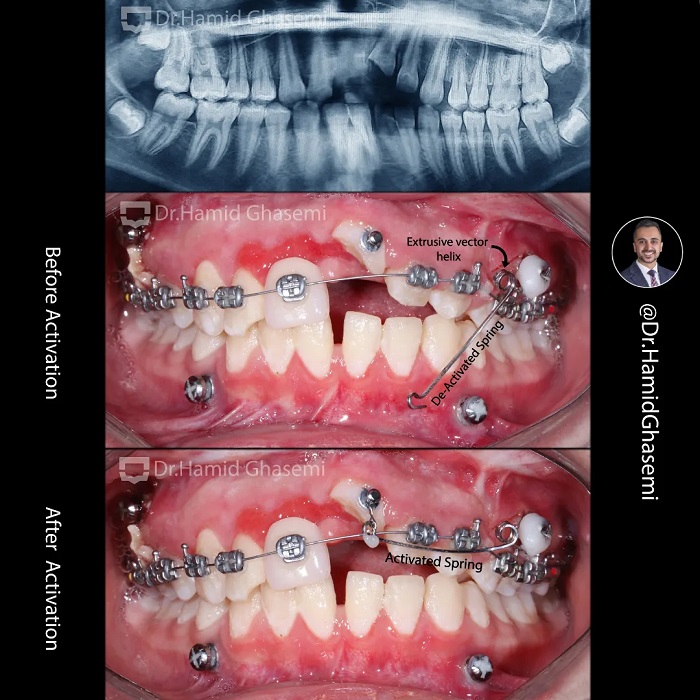

This is a case with history of traumatic accident to the face which caused Lefor I fracture + nasal bone fracture + multiple fractures of both arches + inrusive displacement of front teeth. Thanks to my dear friend @drkianiofficial for taking care of all surgical procedures which includes fixation of Lefort I and multiple fractures within the arches + nasal bone repair simultaneously and reffering the case for post surgical orthodontic force eruption of front teeth. Cantilever spring with double extrusive helix anchored to the surgical screw used to apply extrusive force to the front teeth. Take note on 👉👉 1.The distance of helix to the achorage unit (surgical screw), 2. Orientation of helix and 3.The distance of spring hook to the upper central incisor before activation which are the 3 key points of spring design